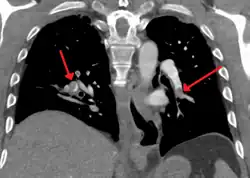

CT pulmonary angiogram

Example of a CTPA, demonstrating a saddle embolus. The white area above the center is the pulmonary artery, opacified by radiocontrast. Inside it, the grey matter is blood clot. The black areas on either side are the lungs, with around it the chest wall. | |

A normal CTPA scan will show the contrast filling the pulmonary vessels, appearing as bright white. Any mass filling defects, such as an embolus, will appear dark in place of the contrast, filling/blocking the space where blood should be flowing into the lungs.

On CTPA, the pulmonary vessels are filled with contrast, and appear white. Any mass filling defects (embolus or other matter such as fat) appears darker. Ideally, the scan should be complete before the contrast reaches the left side of the heart and the aorta, as this may mean contrast has drained from the pulmonary arteries, or require a larger dose of contrast media.[12]